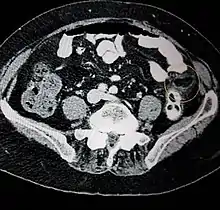

Ultrasound and CT scans are the normal means of positive diagnosis of Epiploic Appendagitis. Ultrasound scans show "an oval, non-compressible hyperechoic mass with a subtle hypoechoic rim directly under the site of maximum tenderness".[4] Normally, epiploic appendages cannot be seen on CT scan.[4] After cross-sectional imaging and the increased use of abdominal CT for evaluating lower abdominal pain, EA is increasingly diagnosed. Pathognomonic CT scan data represent EA as 2–4 cm, oval shaped, fat density lesions, surrounded by inflammation. Contrasting with diverticulitis findings, the colonic wall is mostly unchanged.